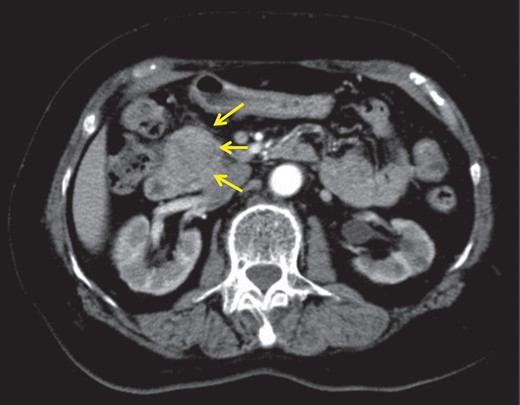

Computed tomography showed a 35-mm wide hypervascular tumour close to the main pancreas duct at the pancreas head (Fig. 1). In addition, a 20-mm right adrenal mass and calcification of both the renal pelvis were detected. Ultrasonography of the neck revealed a 13-mm wide adenomatous nodule. Magnetic resonance imaging of the pancreas showed a well-circumscribed nodule, 35 mm in diameter, with high intensity on T2-weighted image.

Abdominal enhanced computed tomography revealed hypervascular tumour, 3.5 cm in diameter at the pancreas head.